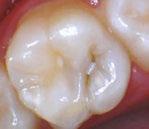

Figure 1: Preoperative periapical radiograph of tooth No. 30 with a large radiolucent lesion approximating the distal pulpal horn and a smaller radiolucent lesion closer to the mesial marginal ridge Figure 3: Conservative removal of all carious dentin on all axial walls and pulpal floor. No clinical pulpal exposure noted, but likely very close to distal buccal pulp horn Figure 2: Large active carious lesion involving the entire distal buccal cusp and surrounding aspect of tooth No. 30. Smaller Class VI lesion located on the mesial lingual cusp on No. 30 Figure 4: Placement and curing of two separate thin layers of NeoLINER over the dentin. Image depicts the NeoLINER following the indirect pulp cap of tooth No. 30